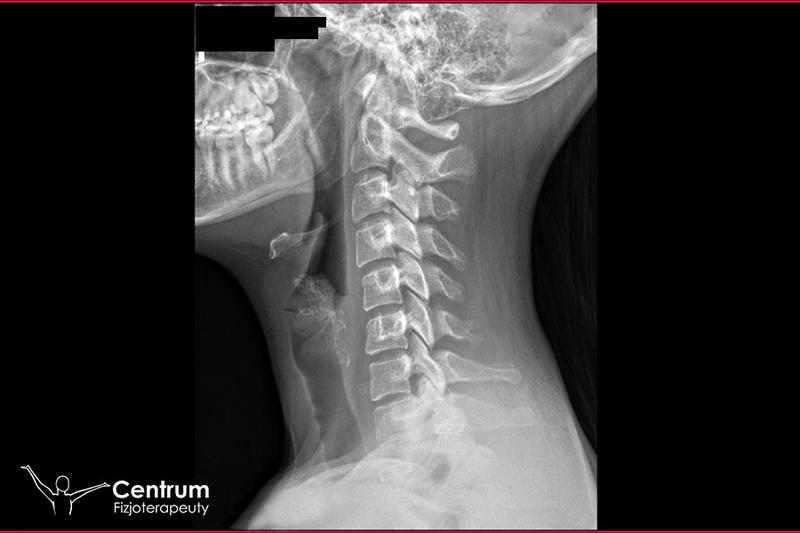

Fakt, iż drętwienie rąk może zwiastować coś poważniejszego, jak udar mózgu czy stwardnienie rozsiane, niepokoi wielu ludzi. Udar występuje nagle, a drętwienie najczęściej dotyczy tylko jednej strony ciała. Jednak nie ma potrzeby panikować! Zwykle drętwienie rąk wynika z takich czynników jak zespół cieśni nadgarstka, problemy z kręgosłupem, nadmiar stresu, czy po prostu niewłaściwa postawa podczas snu. Warto zatem przyjrzeć się tym objawom i przypomnieć sobie, ile razy mrowienie czy kłucie w rękach dawały się we znaki podczas intensywnego korzystania z komputera. Mówią, że najlepszym lekarstwem na drętwienie jest krótka przerwa na rozprostowanie kości!